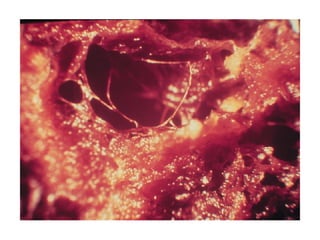

圖片出處: C K  網站